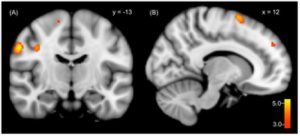

Figure 1: fMRI of DID brain activity

fMRI scans display a significant increase in regional cerebral blood flow in the emotional or traumatic alters’ brains compared to the normal alters brains. The emotional alter displays increased activation of areas that deal with processing sensory information and motor activity while the normal one appears stable [5].